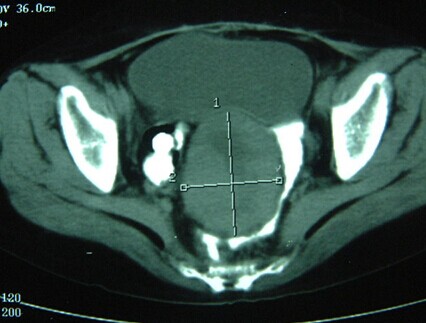

CT显示子宫癌治疗前

女性,54岁,2002年4月21 日入广州复大肿瘤医院。一个月前,因下腹肿胀在印尼接受了剖腹探查,术中发现肿瘤累及邻近组织和器官,未能予以切除。入院后,先给与经皮冷冻和血管介入区域性化疗,2周后给予手术探查,在冷冻协助下,将肿瘤包括子宫、附件和部分受累肠管全部切除。术后再给予区域化疗3次。患者无病生存至今已12年。